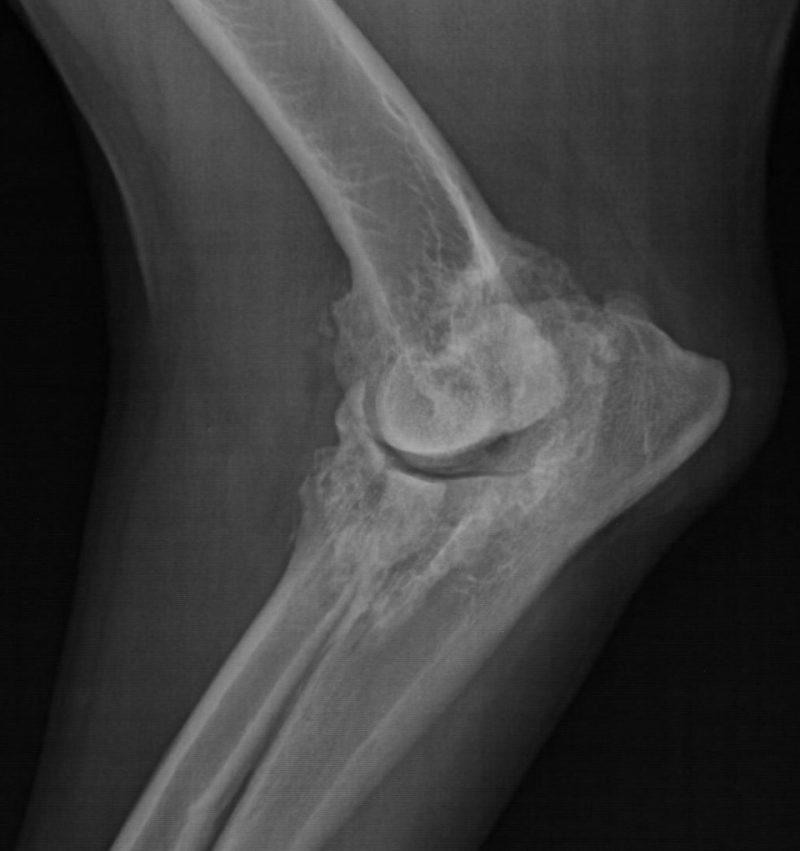

Nichts geht mehr? Urmels neue Menschen ergreifen den letzten Strohhalm. Ende April 2017 wird Urmel von ihrer Pflegerin Fatma nach Schweinfurt gefahren, um sie hier im Tiergesundheitszentrum näher zu untersuchen. Nach einer Gangbildanalyse (die bei einem so schwerfällig und nur mit Unterstützung einer Tragehilfe laufenden Hund natürlich nur eingeschränkt möglich ist) werden nach der anschließenden etwa zweistündigen orthopädischen Untersuchung aller Gelenke noch weitere Röntgenbilder von den Gelenken angefertigt, die in der Türkei nicht untersucht worden sind. Es zeigt sich, dass der Zustand noch schlechter ist als eh schon befürchtet: Urmel hat auch Arthrosen an der Wirbelsäule und weiteren Gelenken. Schließlich werden Urmel insgesamt 62 Berlock-Goldimplantate (das sind kleine spulenförmige Goldimplantate aus Dänemark) implantiert.

Infolge einer Gewichtsverlagerung bei solchen an einem Gelenk schwer gehandicapten Hunden kommt es über die Monate zu Folgeschäden an anderen Gelenken. Diese Schäden können sich bis zu den Zehengelenken ausdehnen. Häufig sehen wir dabei Arthrosen an den Zehengrundgelenken. Nicht selten sind die Sesambeine dieser Zehen frakturiert, durch Überlastung richtiggehend zerbröselt. Gerade solche Schäden aber werden leider zu oft übersehen. Wird eine solche Sesambeinfraktur übersehen, lahmt der Patient trotz aller weiteren Maßnahmen meist weiter. Da nutzt auch die beste Rekonstruktion der Patella am Knie nichts.